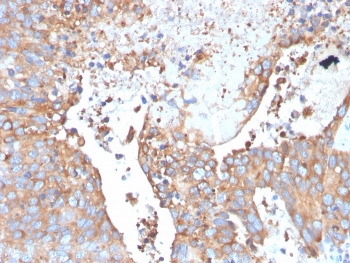

IHC staining of FFPE human urothelial carcinoma with Uroplakin 1B antibody. HIER: boil tissue sections in pH 9 10mM Tris with 1mM EDTA for 20 min and allow to cool before testing.